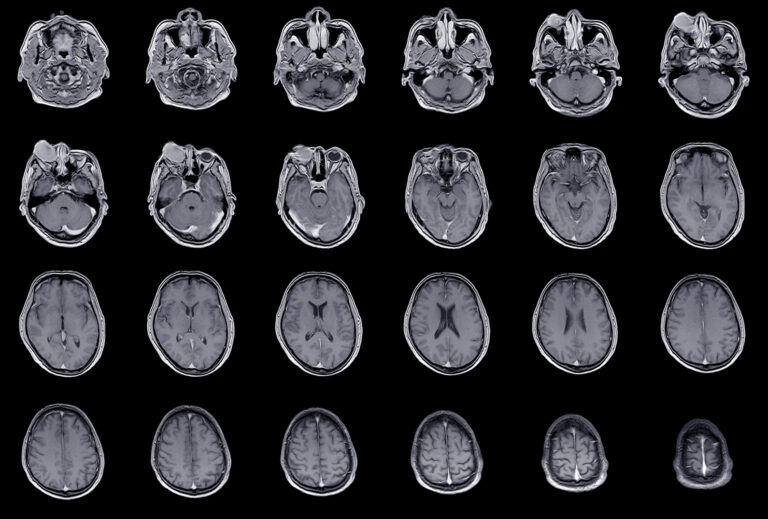

Akne ist die weltweit häufigste dermatologische Erkrankung und wird unter anderem systemisch mit Retinoiden behandelt. Isotretinoin und Co. sind nicht nur teratogen, es sind auch Interaktionen mit anderen Arzneimitteln möglich. Kontraindiziert ist beispielsweise die Kombination von Tetracyclin, denn ein Pseudotumor kann die Folge sein.